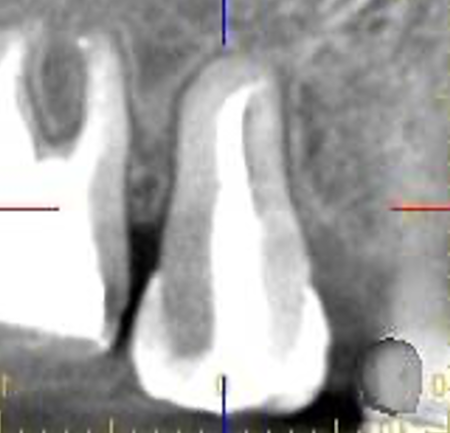

| STEP3 移植後レントゲン | STEP4 5ヶ月後レントゲン (歯槽硬線と歯根膜腔が認められる) |

![]() |